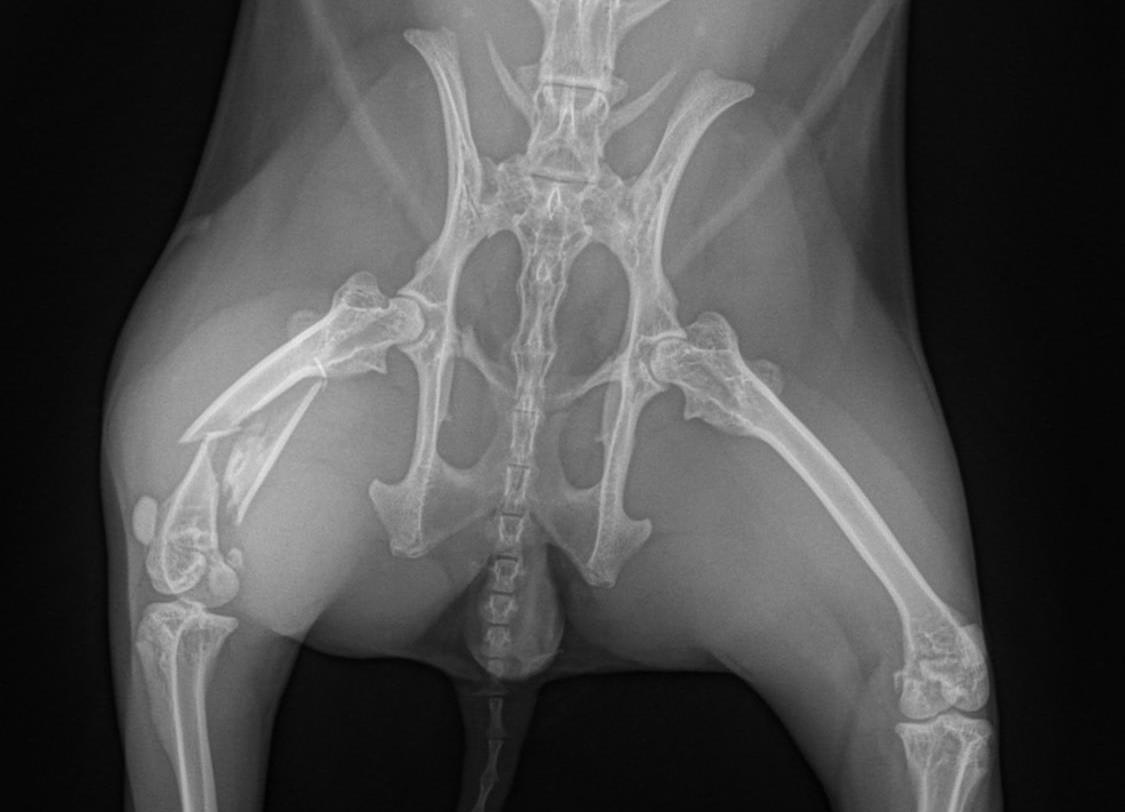

X-rays revealed the diagnosis: her femur (thigh bone) was shattered.